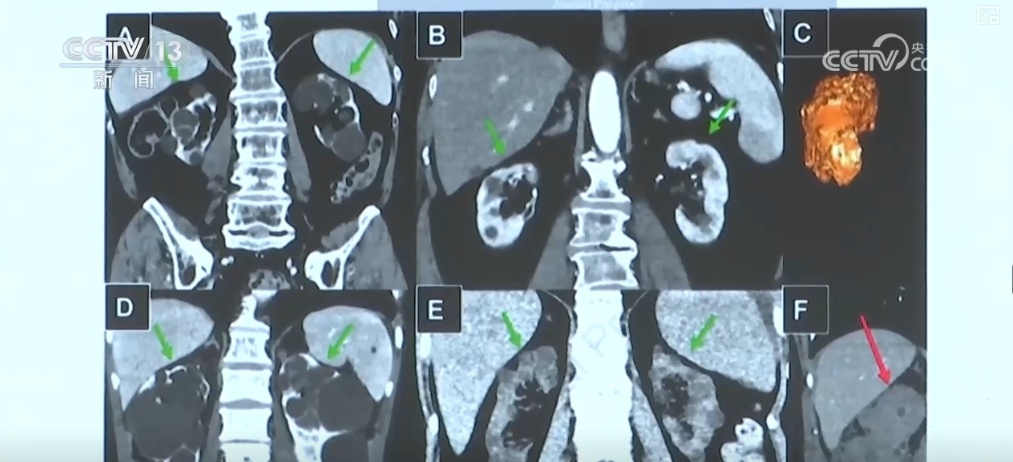

北京协和医院院长、中国罕见病联盟副理事长张抒扬介绍,他们在北京协和医院组织了多学科的会诊平台,让全国多学科专家一起为罕见病一个患者或一个家庭,来提供最精准的诊断和治疗。从对罕见病患者的诊治,过去平均确诊时间要在4年,到现在对来医院的罕见病患者诊断在4周之内。